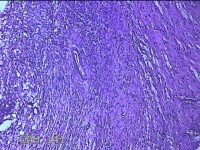

左侧卵巢囊肿⑴

性别

女

年龄

34岁

临床诊断

左侧卵巢子宫内膜异位囊肿

一般病史

下腹痛3小时入院。

标本名称

大体所见

灰白暗红色囊性肿物8x2.5x0.7cm一个,表面糜烂,部分已切开,囊内容物已流失,囊壁厚0.1cm。

图2